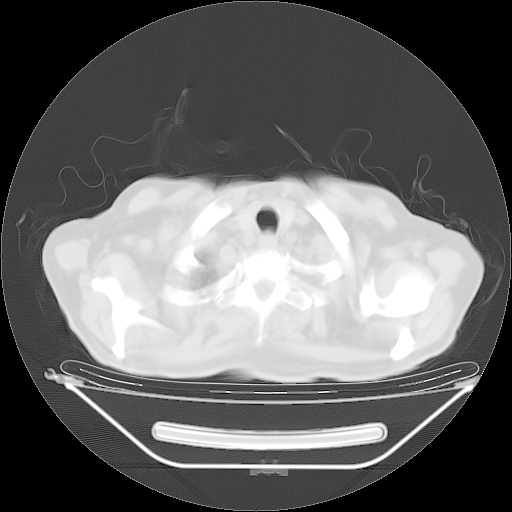

今天复查肺部CT,发现双肺广泛磨玻璃样改变。所以我把3月19日和5月9日相隔50天的肺部CT上传。请大家会诊。

5月9日肺部CT(在4月27日齐鲁医院肺部CT描述部分肺组织磨玻璃样改变,12天后肺组织广泛磨玻璃样改变)

2009年5月9日肺部CT

大致读了系列胸部CT:纵隔窗无明显异常,肺窗:从4、27至今:主要是双肺中下野外带可见毛玻璃样改变,目前处于急性肺泡炎阶段,至于原因考虑1、结替组织或胶原血管性疾病所致?2、恶性疾病如恶组在肺部所致的表现或细支气管肺泡癌?3、药物或其它原因如肺蛋白沉着症所致肺泡炎目前不太可能?总之,明天就去请我院的呼吸科、感染科、血液科和临免专家会诊哈。